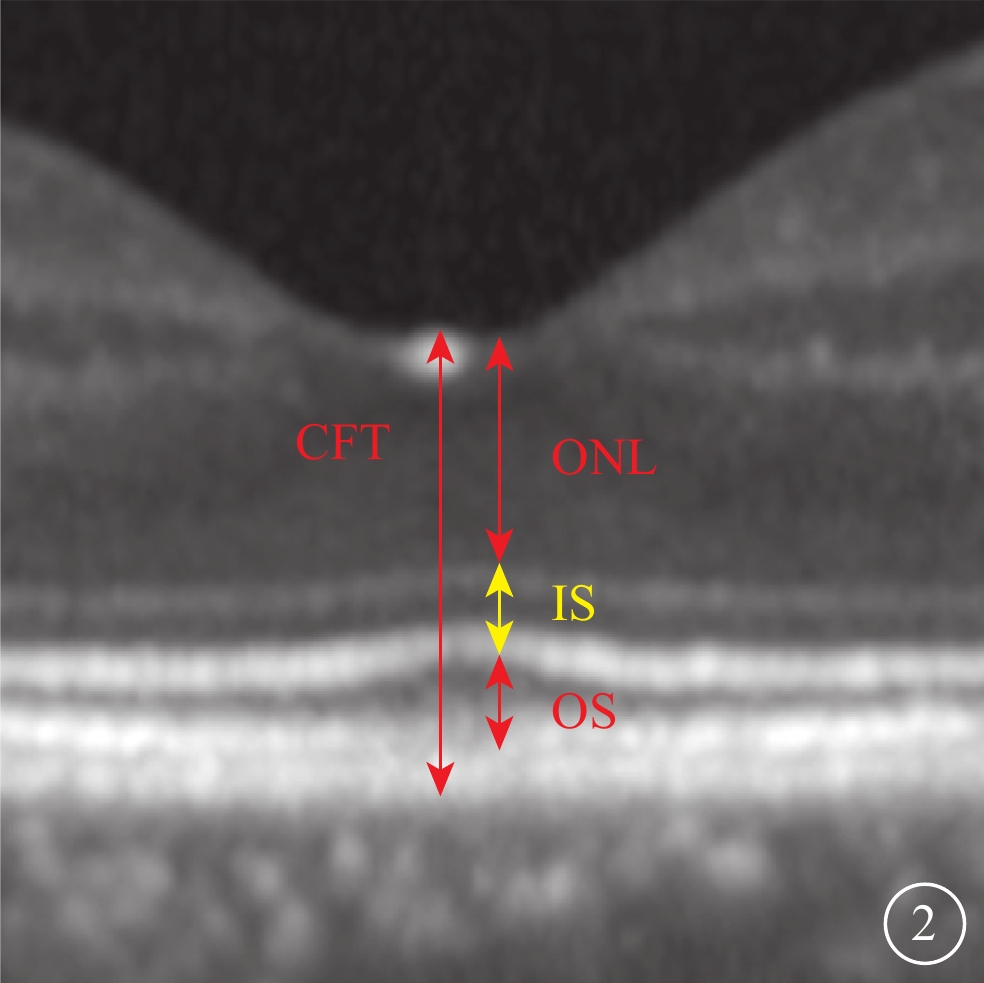

采用法國光太Supra Scan 577 nm多點掃描距陣激光器的持續激光模式或微脈沖激光模式。CLT治療參數:曝光時間0.05 s,光斑直徑100 μm,能量50~60 mW,光斑數量18~27個。SLT治療采用Supra Scan 577 nm微脈沖激光模式。治療參數:曝光時間2.00 ms,占空比5%,光斑直徑160 μm,能量250~400 mW。兩種治療方式的治療區域均為滲漏點周圍區域。所有治療均由同一位經驗豐富的眼底病醫生完成。由一位有經驗的特檢科醫生采用SD-OCT儀(Heidelberg Eye Version 1.8.6.0頻域OCT系統),對中心凹進行9 mm橫、豎單線掃描,以及黃斑區6 mm×6 mm范圍內25個斷面橫掃描,并采用隨訪模式保證每次隨訪掃描時的位置不變。選取經過中心凹的水平方向掃描圖像用于視網膜微結構評估。定性評估包括中心凹下EZ、嵌合體帶(IZ)的完整性和RPE平滑性。EZ、IZ完整性分為完整或不完整,不完整定義為OCT下相應層次連續性中斷(圖1A,1B)。RPE平滑性分為平滑或粗糙,粗糙定義為RPE局部隆起(圖1C)、RPE脫離(PED)(圖1D)、RPE增厚。定量評估包括中心凹視網膜厚度(CFT)和外核層(ONL)、內節(IS)、OS厚度。CFT定義為內界膜(ILM)內界至RPE外界的垂直距離。ONL定義為ILM外界至外界膜(ELM)內界的垂直距離。IS定義為ELM至EZ外界的垂直距離。OS定義EZ外界至RPE內界的垂直距離(圖2)。上述所有評價指標均由兩位眼科醫生分別盲態下單獨讀取,其中定量指標取兩者平均值納入統計,定性指標若存在爭議進一步討論并確定最終結果。

圖2

視網膜各層厚度測量示意圖

圖2

視網膜各層厚度測量示意圖

采用法國光太Supra Scan 577 nm多點掃描距陣激光器的持續激光模式或微脈沖激光模式。CLT治療參數:曝光時間0.05 s,光斑直徑100 μm,能量50~60 mW,光斑數量18~27個。SLT治療采用Supra Scan 577 nm微脈沖激光模式。治療參數:曝光時間2.00 ms,占空比5%,光斑直徑160 μm,能量250~400 mW。兩種治療方式的治療區域均為滲漏點周圍區域。所有治療均由同一位經驗豐富的眼底病醫生完成。由一位有經驗的特檢科醫生采用SD-OCT儀(Heidelberg Eye Version 1.8.6.0頻域OCT系統),對中心凹進行9 mm橫、豎單線掃描,以及黃斑區6 mm×6 mm范圍內25個斷面橫掃描,并采用隨訪模式保證每次隨訪掃描時的位置不變。選取經過中心凹的水平方向掃描圖像用于視網膜微結構評估。定性評估包括中心凹下EZ、嵌合體帶(IZ)的完整性和RPE平滑性。EZ、IZ完整性分為完整或不完整,不完整定義為OCT下相應層次連續性中斷(圖1A,1B)。RPE平滑性分為平滑或粗糙,粗糙定義為RPE局部隆起(圖1C)、RPE脫離(PED)(圖1D)、RPE增厚。定量評估包括中心凹視網膜厚度(CFT)和外核層(ONL)、內節(IS)、OS厚度。CFT定義為內界膜(ILM)內界至RPE外界的垂直距離。ONL定義為ILM外界至外界膜(ELM)內界的垂直距離。IS定義為ELM至EZ外界的垂直距離。OS定義EZ外界至RPE內界的垂直距離(圖2)。上述所有評價指標均由兩位眼科醫生分別盲態下單獨讀取,其中定量指標取兩者平均值納入統計,定性指標若存在爭議進一步討論并確定最終結果。

圖2

視網膜各層厚度測量示意圖

圖2

視網膜各層厚度測量示意圖